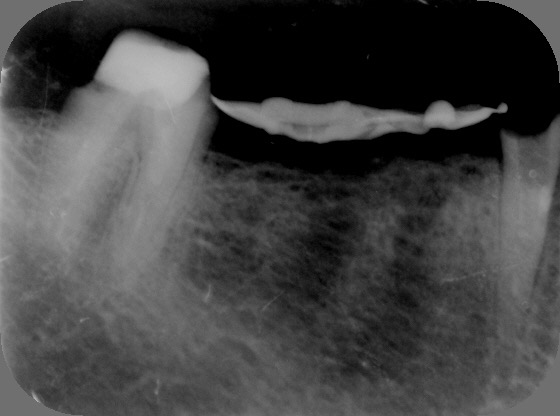

Autores: PRÓLOGO Asimismo, desde el punto de vista pedagógico, el profesional nobel en la materia tiene a su alcance la posibilidad de corregir cualquier posición implantaría en el ordenador, planear los provisionales y plasmarlos en la bio réplica antes de tocar al paciente a operar. Todos estos razonamientos nos llevan a presentar un caso de condiciones muy favorables para poner en práctica estos métodos como primer acercamiento a una Odontología Digital de alta calidad, con medios informáticos, que ya están presentes en la profesión de hoy en día, y será la protagonista única del futuro. Por otro lado, después de numerosos estudios que nos llevan a plantear el “gap” entre implante y pilar(abuttment), como principal responsable de la periimplantitis dado que la microbiota presente en el mismo es imposible de limpiar y en su presencia la cortical ósea reacciona reabsorbiéndose, nos ha llevado a utilizar implantes monobloc ya que los ejes implantarios y protéticos coincidían, y nos permitían su uso. Además, el circonio, ha mostrado a la luz de estudios muy recientes, una preservación y adhesión de los tejidos blandos superiores al titanio, tanto en su tratamiento de superficie de la rosca como a nivel gingival. DESARROLLO Paciente varón de 68 años, con antecedentes de radio/quimioterapia cinco años antes, con Rehabilitación Oral de los cuatro cuadrantes, con una Oclusión Mutuamente Compartida conservada, (REF.8) la que fracasa en el cuadrante 4, 19 años después. El mismo presentaba un puente de porcelana sobre circonio con pilares en 44 y 47, reemplazando el edentulismo de 45 y 46. Se produce la fractura del PM del 44, y ante una endodoncia antigua y corta, se decide implantar las zonas edéntulas, conservando temporariamente los pilares, hasta producida la oseointegración, para entonces también exodonciar el 44. DIAGNÓSTICO Tomamos impresiones del maxilar antagonista, Arco Facial Estático y realizamos montaje del mismo mediante la sistemática ARTEX. Producimos la relajación del músculo Pterigoideo Externo, para obtener la ORC (Oclusión en Relación Céntrica) mediante el método de Laminillas de Long, basado en el concepto de INERVACIÓN RECÍPROCA. Esto nos permitirá montar el maxilar inferior, tanto en su forma de: La primera para practicar la cirugía guiada y comprobar su eficacia, y el modelo de yeso para ser escaneado y confeccionar la GUÍA QUIRÚRGICA. La Biorréplica la obtenemos transformando los archivos DICOM que nos da el CBCT en archivos STL, y a partir de ellos, mediante una tecnología de PROTOTIPADO RÁPIDO, la obtención de un objeto físico en 3D a través de la aglutinación selectiva de una sucesión de capas de polvo. Procedemos a montar la biorrèplica y el modelo de yeso del caso. Podemos verificar la exactitud de las medidas del hueso residual en la bio réplica y compararlas con el scanner. Arrojando un resultado de 8,5 mm de cortical externa a cortical externa. Pudiendo también medir la distancia hasta el dentario. y comparar gracias a la ventana lateral de la biorréplica Dándonos 22mm de distancia. Con lo cual deducimos que implantes de 4,1mm por 12 mm serán perfectamente rodeados de hueso. Medimos también la distancia desde oclusal del antagonista, hasta el hueso desnudo. Lo mismo que, mediante la utilización de la guía radiológica, con un material radiolúcido colocado en gingival de la misma, podemos medir la altura de la encía. Con lo cual podemos calcular la altura del pilar. Es entonces cuando con el programa COC Diagnostix se realiza la programación final: Obteniendo no solo la ubicación, largo, ancho y ángulo de los implantes sino también los provisionales mediante CAD CAM. Ya entonces podemos hacer la práctica quirúrgica en la bio réplica, mediante la guía quirúrgica, instalando los implantes de prueba que no serán los de circonio, ya que la casa no cuenta con ellos, pero si otros de las mismas dimensiones. TRATAMIENTO Entramos ya en la cirugía propiamente dicha. Antisepsia de la zona a operar y zonas anexas. Comprobación del perfecto ajuste e inmovilidad de la G.Q. en boca durante la cirugía. Marcado de la encía y perforación de la cortical. Visión a través de la Guía de la mínima intervención anterior. Comprobación sin Guía. Incisión mínima mesio distal, para apartar y conservar encía queratinizada. Secuencia de drills, perforando a profundidad requerida Observación del Mínimo Trauma Implantes Strauman de Zirconio Monoblock en blíster y montádo en contrángulo reductor. Instalación controlando torque con contrángulo reductor. Comprobación clínica. Comprobación Radiográfica y con Guía. Toma de impresiones, y armado de modelos con técnicas de pasividad protética. Montaje. Resultado de las provisionales ejecutadas por CAD CAM Al no estar conformes con el resultado decidimos desechar dichas provisorias y optar por repetirlas. Nuevas provisorias realizadas mediante encerado convencional. Estado de los tejidos blandos. Provisorias en boca. Oclusión de Estímulo Inmediato. Ref.10: Carga inmediata .Alberto y Diego Bechelli. Comprobación mediante CBCT post operatorio Componentes del equipo (En la próxima presentación, mostraremos las coronas definitivas de porcelana sobre circonio, y la desoclusión provocada por una OCLUSIÓN MUTUAMENTE COMPARTIDA, sobre estos implantes y otros seis mas) REFERENCIAS

Realizamos previamente una Rx periapical Dígora (radiovisiografía) y un CBCT (TAC de haz de cono) con férula radiológica, marcando ambas raíces del 46 y la raíz del 45.

FIG: 5-6-7-8

FIG: 9-10-11-12